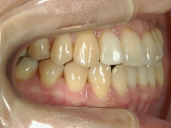

矯正歯科 治療前 右

矯正歯科 治療前 左